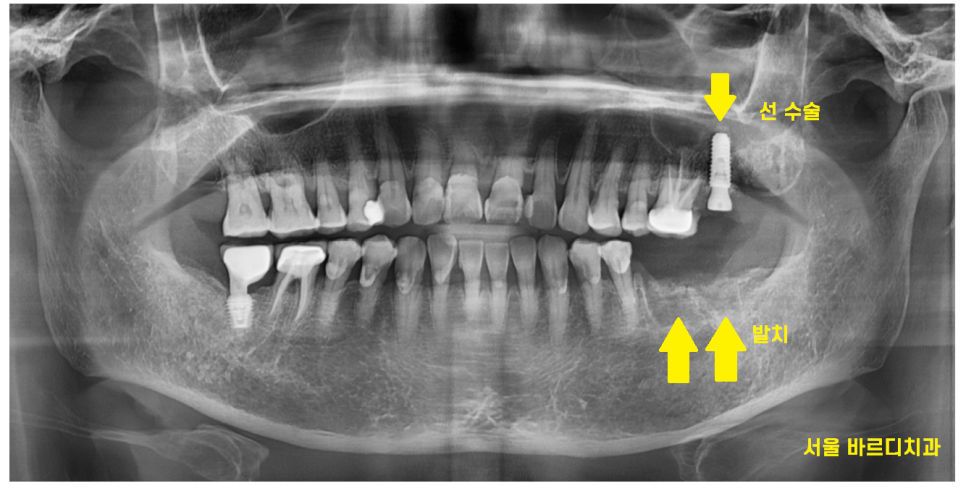

심각한 왼쪽 맨 위 치아 1개를 발치하고

어금니 흔들림 최소화 하기 위하여

어금니 흔들림과 통증이 동반되어

먼저 발치한 윗니

고덕동 치과에서 임플란트를 시행

24.02.16

2개월 뒤 아래 치아 수술도

고덕동 치과에서 임플란트 완료하였습니다.

24.05.08

수술 시점은 달랐지만

윗니 아랫니 완성은 한번에 해드렸는데요.

문제 있는 치아를 속시원하게 발치하고

고덕동 치과에서 임플란트로 진행하였기에

이제 통증으로부터 안녕~

고덕동 임플란트 완성사진입니다.